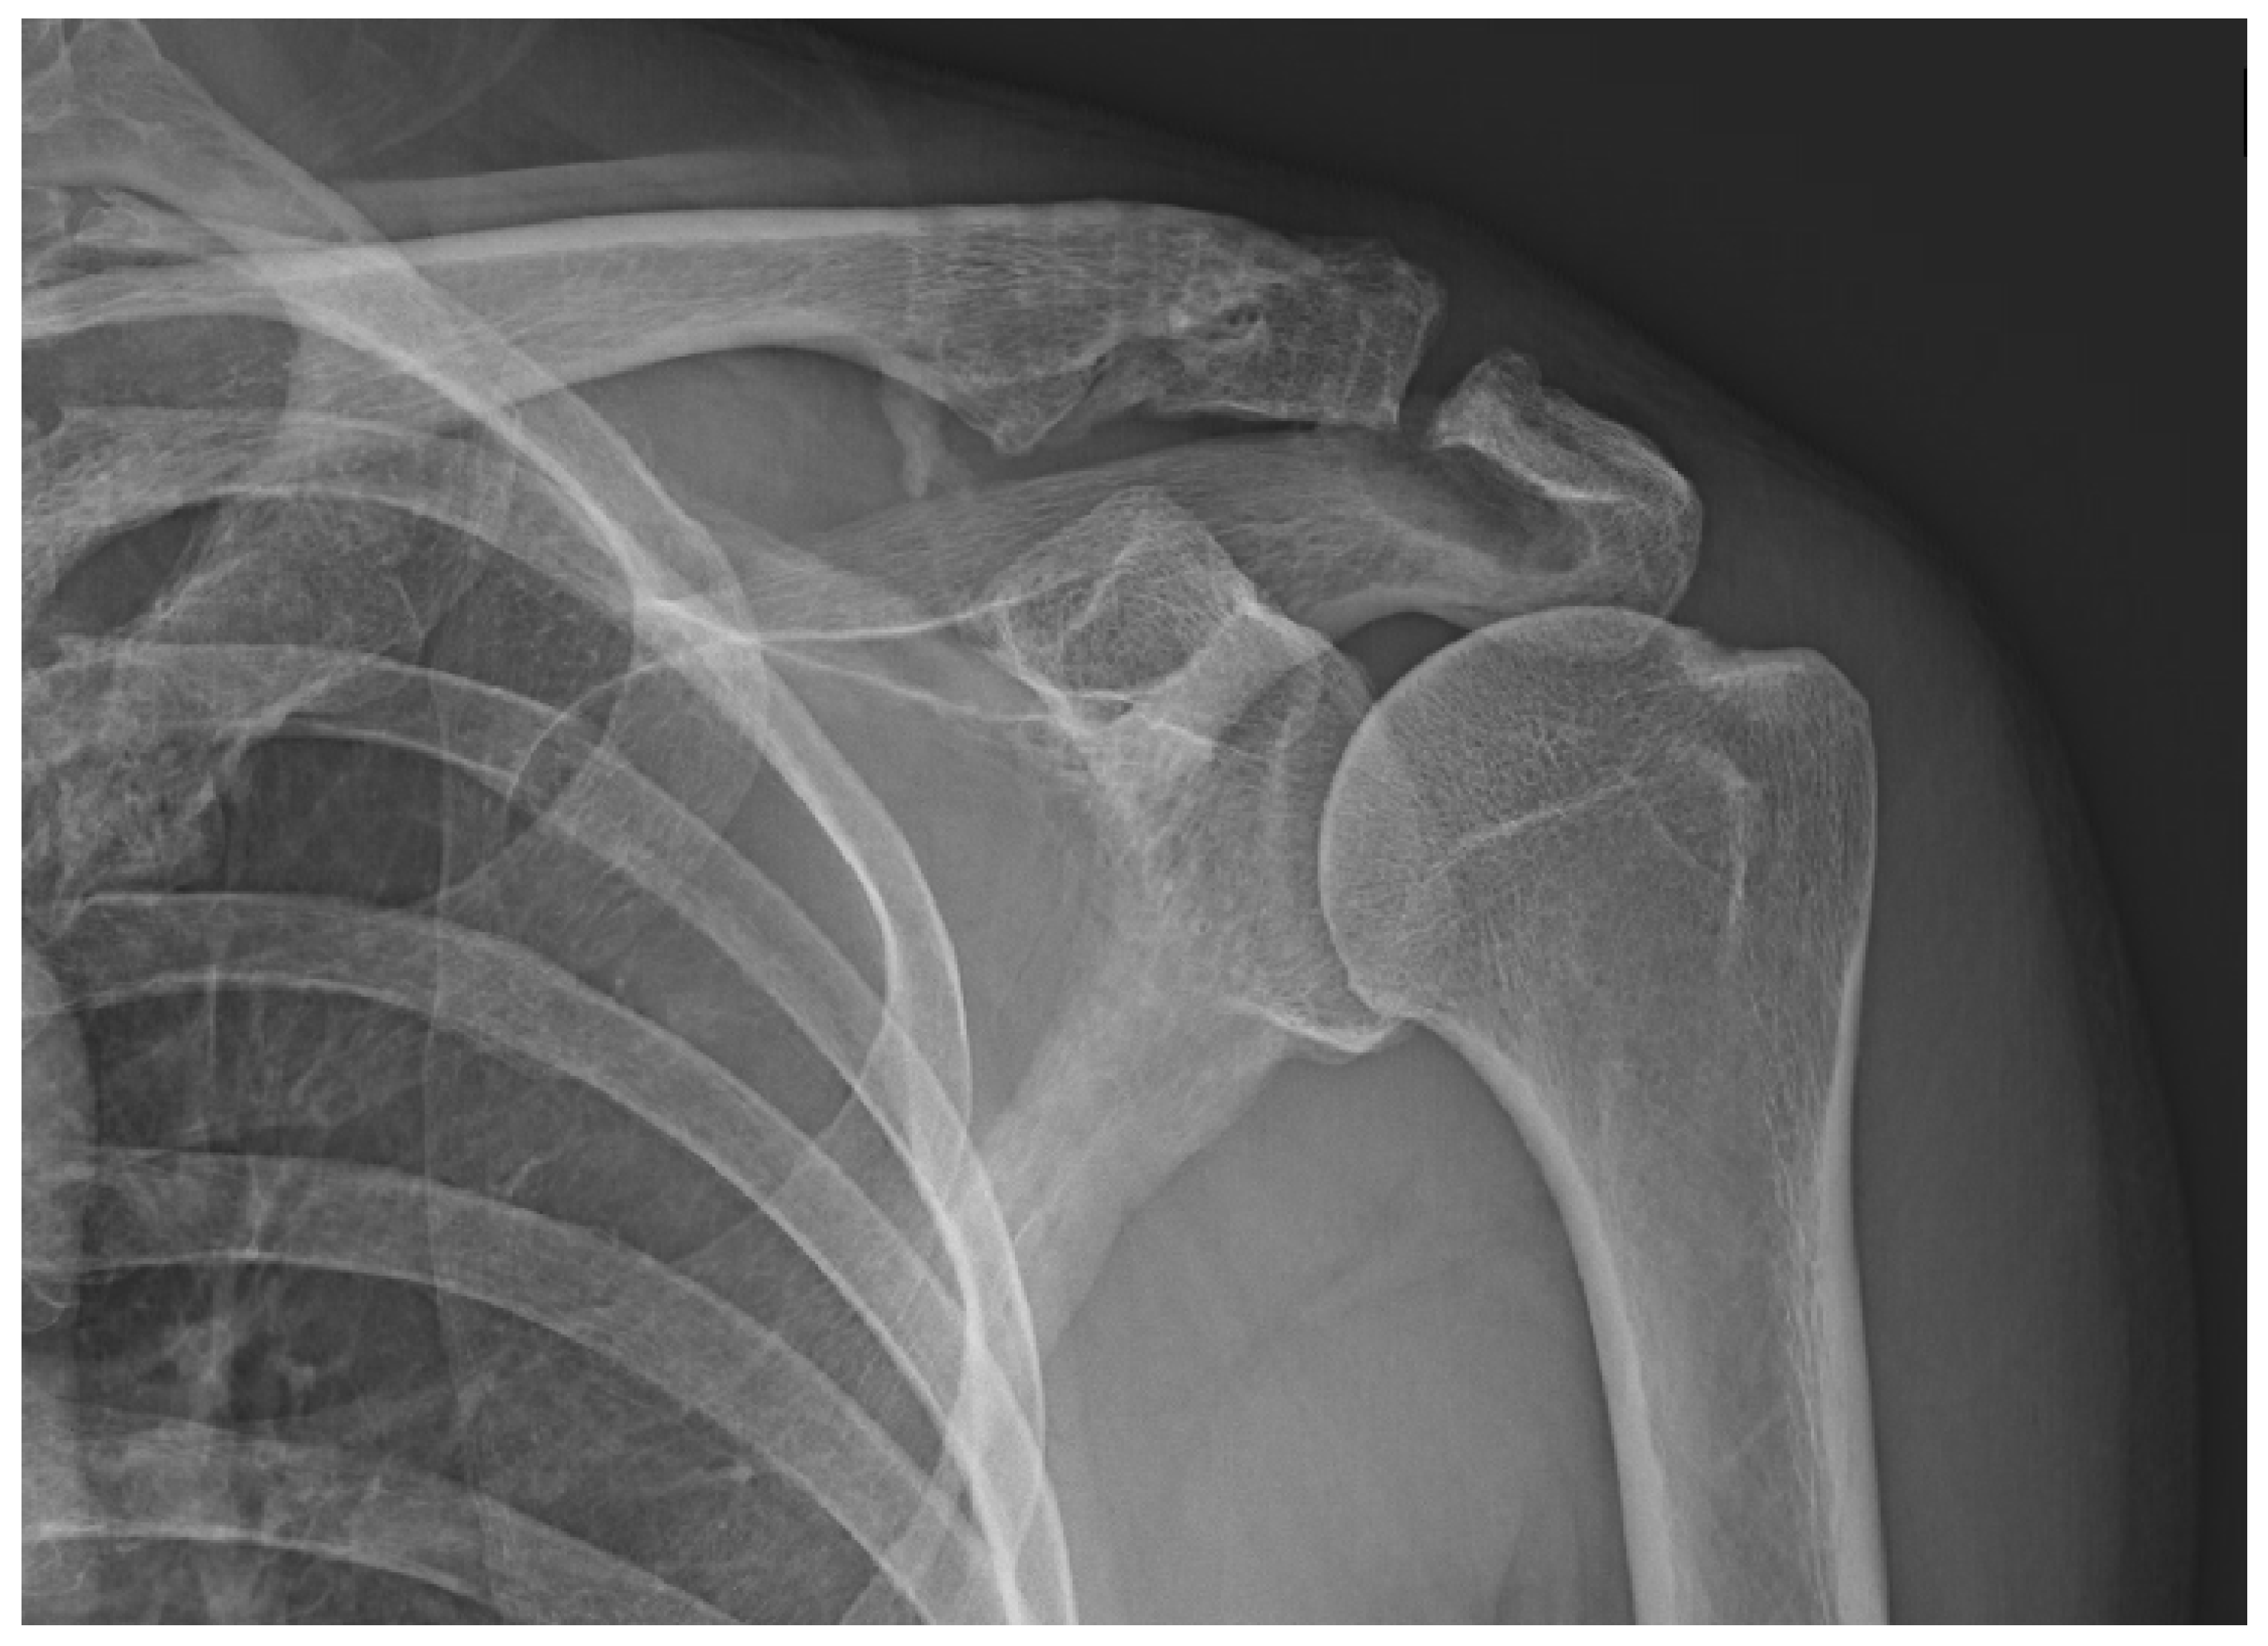

Varying degrees of subacromial erosion occurred in all patients, and acromial fracture occurred in one case in the DCF group and seven cases in the ACD group (Figure 2 and Figure 3). Five (6.7%) cases showed incomplete union and one (1.3%) case showed peri-implant stress fracture in the DCF group (Figure 4 and Figure 5). Four of the five cases of incomplete union showed fracture union without additional surgery during the follow-up period, and one case did not heal at the final follow-up, although the patient did not show any discomfort with non-union (Figure 6). The peri-implant fracture healed with conservative management before plate removal. LOR was observed in nine patients with ACD. Before removing the hook plate, LOR occurred in six patients with ACD. Among these six patients, five showed acromial fracture and one showed serious subacromial erosion (Figure 7). After removing the hook plate, LOR occurred in three patients during the follow-up period. However, none of these patients with LOR among patients with ACD showed tenderness on the acromioclavicular joint or pain during the follow-up period. Regarding acromial fracture, one (1.3%, 1 of 36) case was observed in the DCF group and seven (8.3%, 7 of 33) cases were noted in the ACD group (Figure 4). There was no difference in the incidence of acromial fracture between patients with DCF and ACD (p = 0.066). All eight patients had fracture union without additional surgical treatment during the follow-up period.

Figure 7. Loss of reduction in acute acromioclavicular joint dislocation. (a) With severe acromial erosion; (b) with acromial fracture.